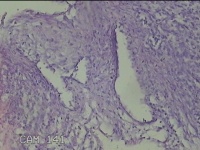

左卵巢囊肿

性别

女

年龄

47岁

临床诊断

左附件囊肿

一般病史

不规则阴道流血20余天。

标本名称

大体所见

灰白暗红色囊壁样组织4.3x1.3x0.3cm一块,表面光滑,因已切开,囊内容物已流失,囊壁厚0.1cm。

良性病变。